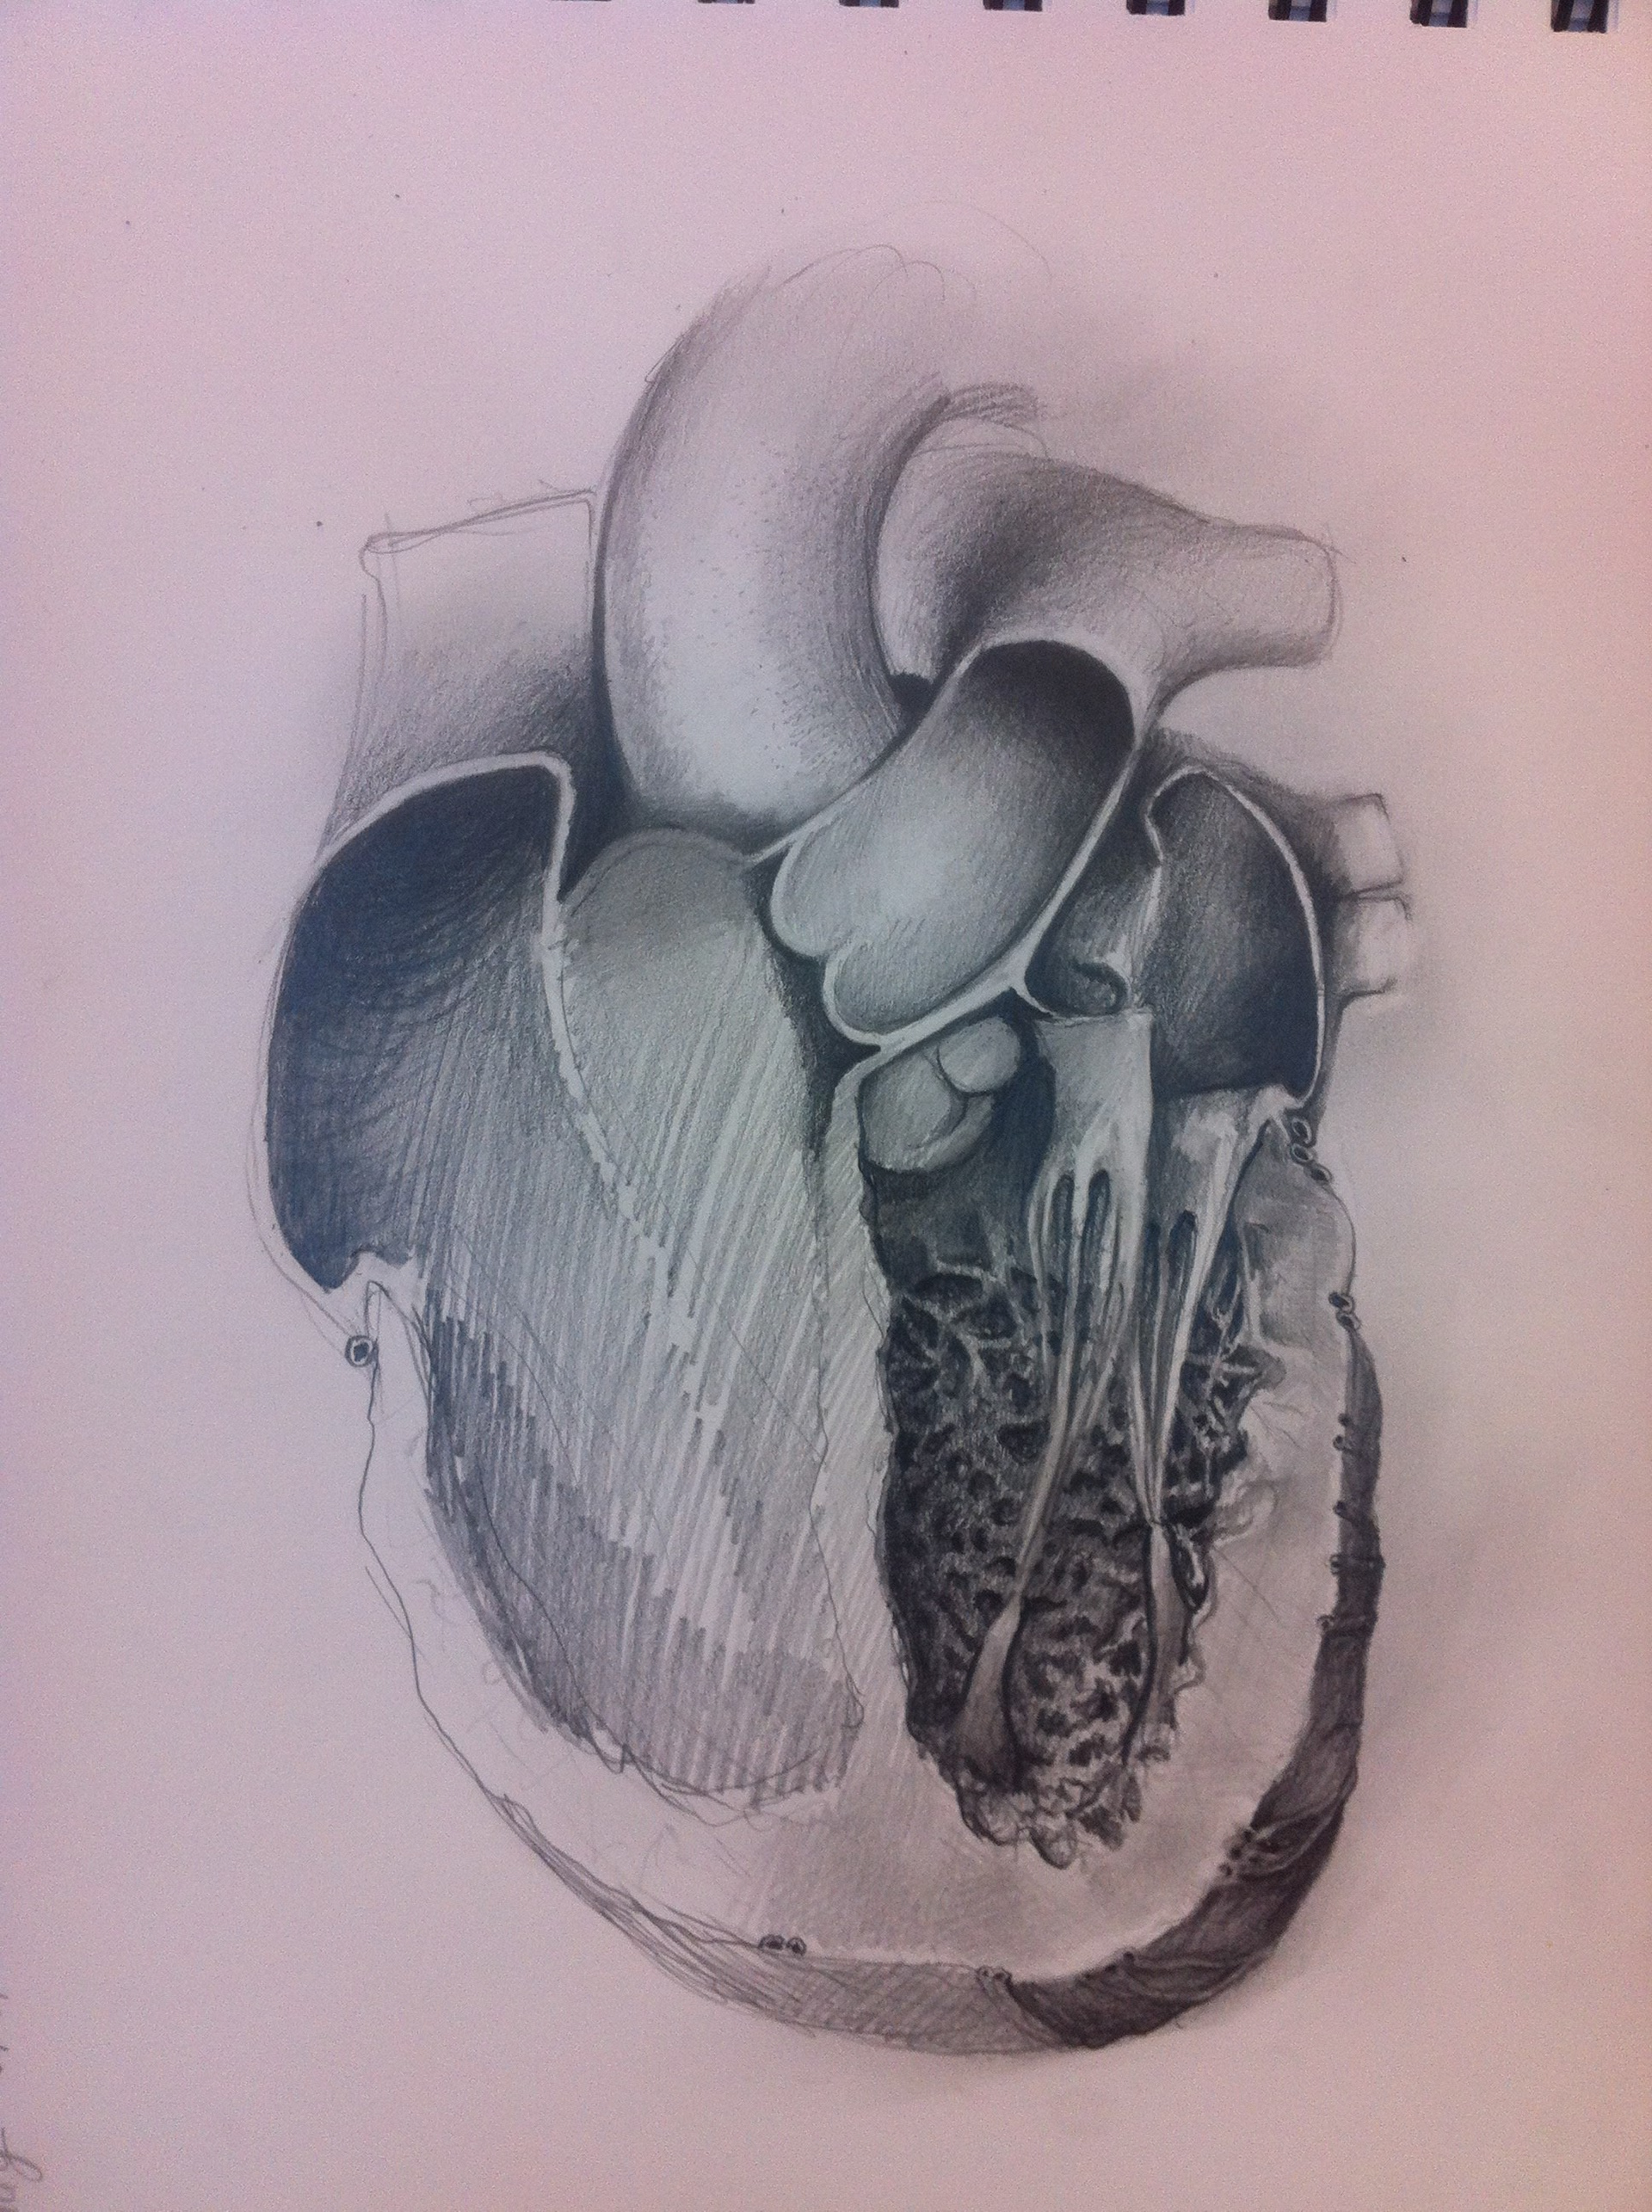

Early concept sketches of the the heart